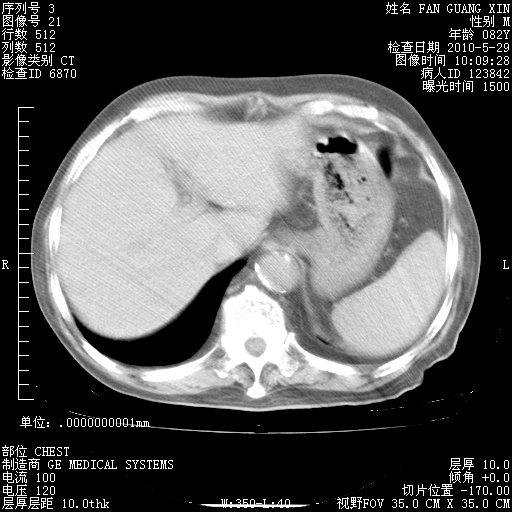

再治疗10天后的肺部CT

再治疗10天后的肺部CT 纵膈窗

阅读此次胸部CT,肺间质渗出性改变较入院时有吸收。目前从体温、白细胞、中性分叶明显增高,肯定存在细菌感染(发生医院感染哦,若无消化道及泌尿系统等感染的依据,肺部感染可能大)。若你院头孢哌酮舒巴坦钠耐药率较高,同意你的方案,若48小时体温仍高,可考虑使用碳青霉稀类抗菌药物,同时可予超声雾化、注意滴数时加大液体量。白蛋白33.30g/L较低哦,需加强营养等支持治疗。